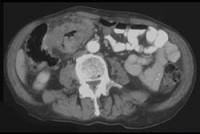

问题 男,45岁,右下腹胀痛、并可触及质硬包块,请结合图像选择最可能诊断()

选项 A.结肠Crohn病 B.结肠癌 C.肠结核 D.结肠淋巴瘤 E.慢性溃疡性结肠炎

答案 B